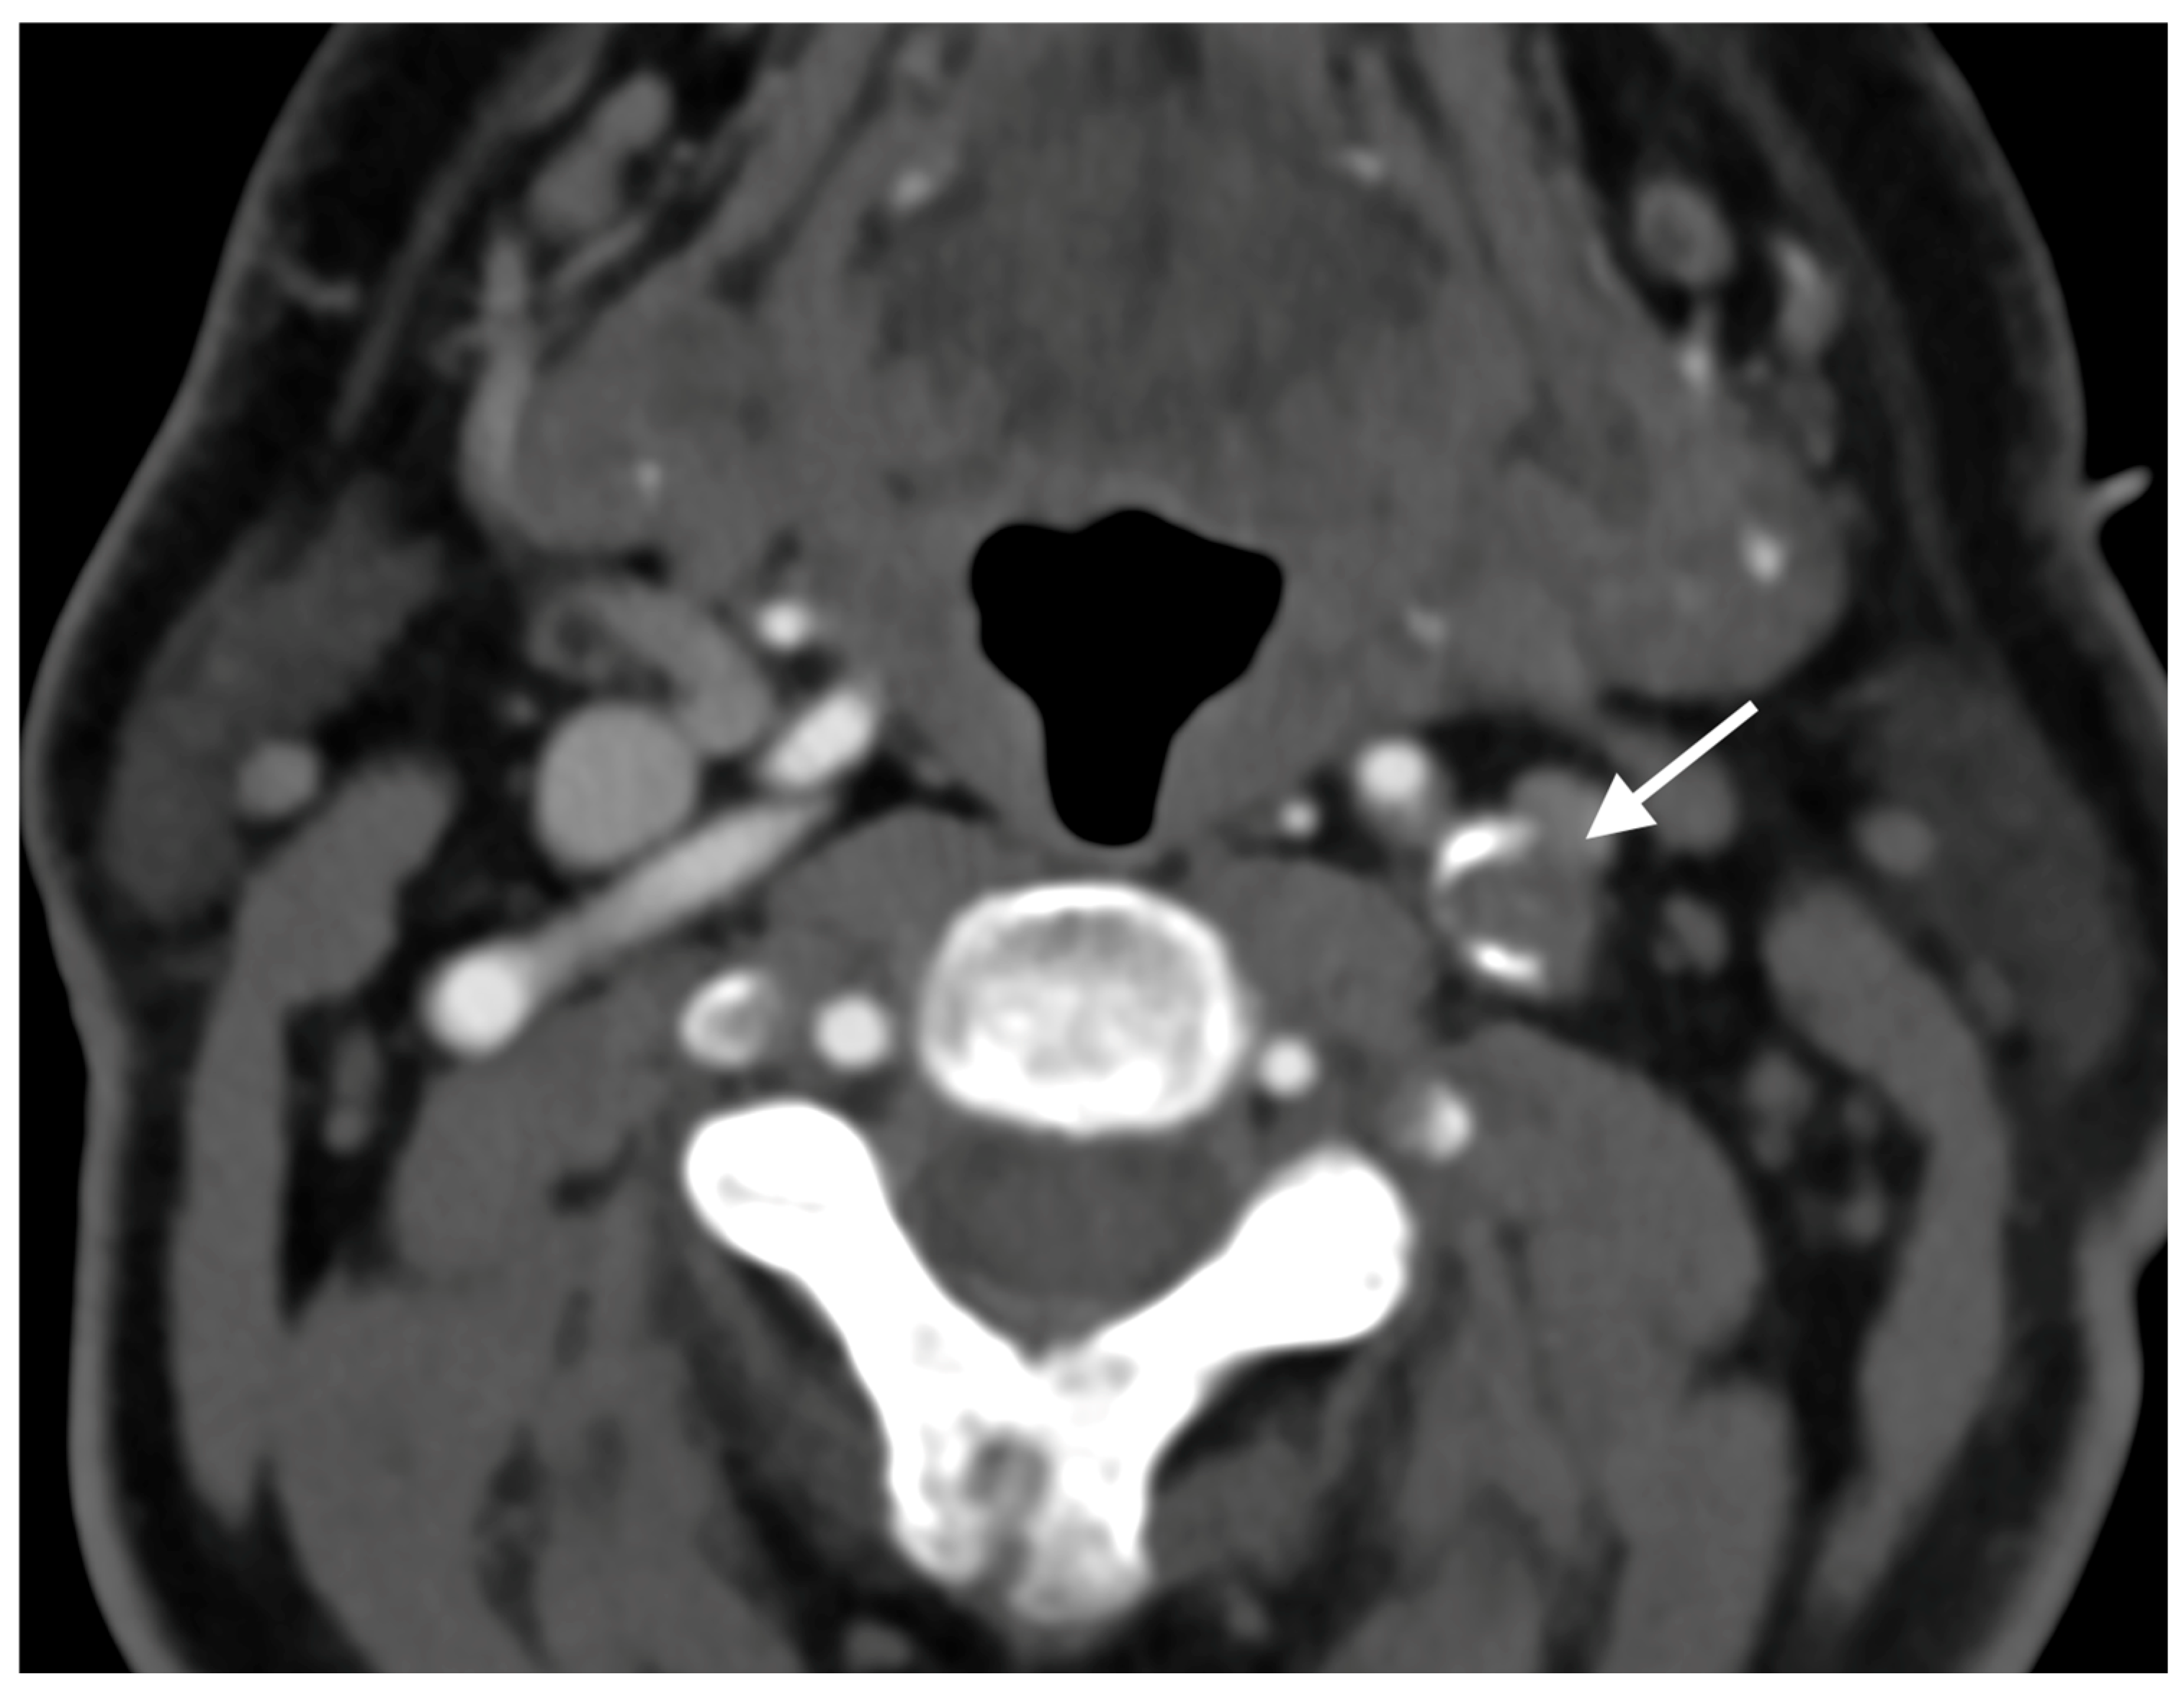

A 67-year-old male patient with a medical history of hypertension, coronary artery disease, and diabetes mellitus type 2 presented to the emergency department reporting an acute onset speech disturbance and weakness of the right upper limb, starting 1 h before his presentation. In the clinical examination, he had a National Institutes of Health Stroke Scale (NIHSS) score of four with mild aphasia, right central facial nerve palsy, and right upper limb paresis; however, his symptoms were completely resolved 20 min after his arrival. The patient underwent an urgent brain MRI scan, showing no acute brain infract and an MR-Angiography scan, which suggested a total left proximal ICA occlusion and a high grade (70%) occlusion of the right ICA. These findings were obtained via CTA, which was also performed urgently (Figure 1). Due to the spontaneous resolution of symptoms with an NIHSS score of 0 during and after the radiologic investigation, the possibility of intravenous thrombolysis was deferred. The patient’s symptoms were attributable to a high-risk TIA and he received clopidogrel combined with aspirin (clopidogrel 300 mg as a loading dose on day 1, followed by 75 mg daily from day 2 and aspirin 100 mg on the first day, followed by 100 mg daily) [8,9]. Afterward, the patient was transferred to the neurology department for further evaluation and continuous vital sign monitoring. During the first day of admission, he suffered further crescendo TIAs (at least six distinctive episodes) with similar symptomatology; however, no hemodynamic trigger was considered possible, raising suspicion of a thromboembolic mechanism of infarction. His NIHSS scoring during every TIA fluctuated from 1 to 4 and rapidly returned to 0 within a maximum time interval of 10 min. The cardiologic investigation with a 24 h Holter monitor and transthoracic cardiac ultrasound was negative. A new brain ΜRI study was conducted 24 h later, which demonstrated multiple ischemic lesions ipsilateral to the occluded internal carotid artery (Figure 2). These findings (negative cardiologic investigation and multiple ischemic lesions ipsilateral to the occluded ICA) raised concerns of an unstable plaque in the ipsilateral ICA on a pseudo-occlusion basis. Consequently, the necessity of performing a DSA in order to re-evaluate the carotid patency and to distinguish between a true occlusion and a possible pseudo-occlusion seemed inevitable. Contrary to the CTA and MRA results, the DSA revealed the “string sign” in the occluded ICA (Figure 1, Figure 3, and Figure 4) and confirmed the pseudo-occlusion. Although this small amount of trickle flow could not effectively perfuse the brain, emboli from the carotid stump could be transported either through the external carotid artery and the collateral circulation to the brain or through the near-occluded lumen and cause distal infarction, the so-called CSS.

Figure 1. Initial CTA demonstrating complete nonattenuation of proximal cervical segment of left ICA.